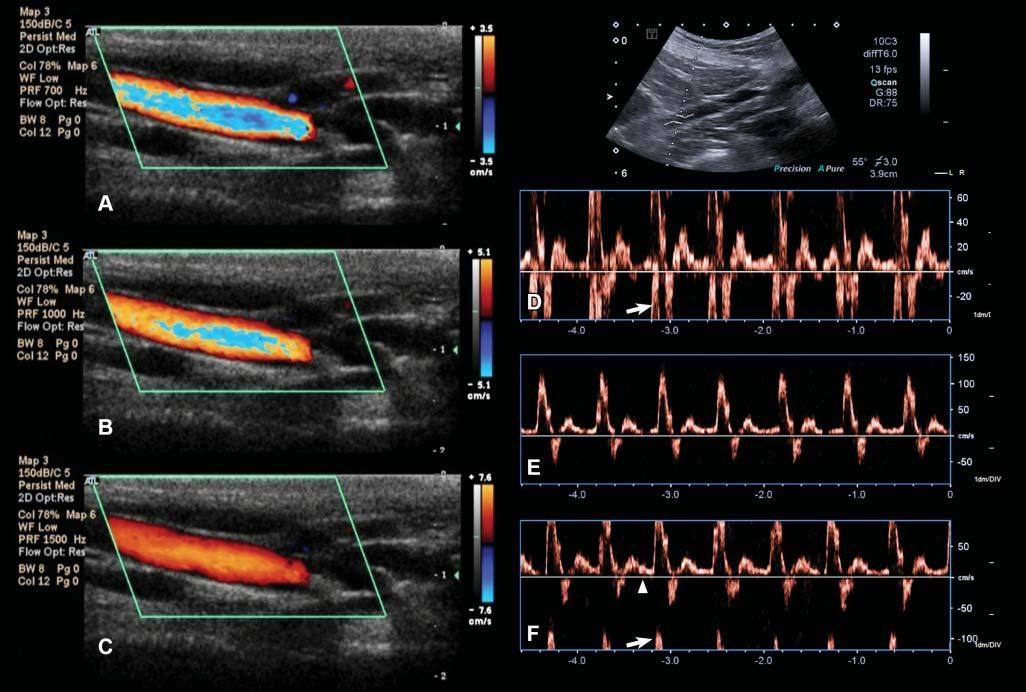

DopplerAliasing

Thisartifactoccursforahigh-velocityflowwhenthe Dopplersamplingrate(i.e.,pulserepetitionfrequency, PRF)islessthantwicetheDopplerfrequencyshift ofthatflow(Hindietal.2013).Aliasingcausesthe

Figure1.24. Aliasingartifact.A: WithcolorDoppler,aliasingappearsasalinearormosaichueinthecenterofa high-flow-velocityvesselandwhenthemeasuringscale(ontheright–3.5cm/sinthiscase)isexceeded. B: Byincreasingthe scaleto5.1cm/s,theartifactislesspronounced. C: Itdisappearscompletelywhenthescaleisincreasedto7.6cm/s. D: With spectralDoppler,aliasingmanifestsitselfasawraparoundoftheflowprofileontheoppositeextremityofthevelocityscale. Themeasuredmaximalvelocityofthisiliacartery(inthedirectionofthetransducer)exceeds60cm/sandisinterpretedas reversed(arrow). E: Increasingthevelocityscale(orpulserepetitionfrequency)to150cm/sallowstheentireflowspectrumto beincluded.Notethatthecalculatedmaximalvelocityofthisarteryexceeds100cm/s. F: Thebaseline(arrowhead)position canalsoberesponsiblefortheonsetofaliasing.Inthiscase,itwasmovedtothepositiveside,reducingthescaleonthatside (maximalvelocityapproximating75cm/s),andresultinginvelocitypeakwraparound(arrow).

high-frequencycomponentoftheflowtowraparound thescale,fromitspositiveornegativeextremity, dependingonitsdirection(Figure1.24).

Aliasingcanbereducedoreliminatedbyincreasing thevelocityscale(whichincreasesthePRF),moving upordownthebaseline,increasingtheDopplerangle (whichdecreasestheDopplershift),orusingalower ultrasoundfrequency.